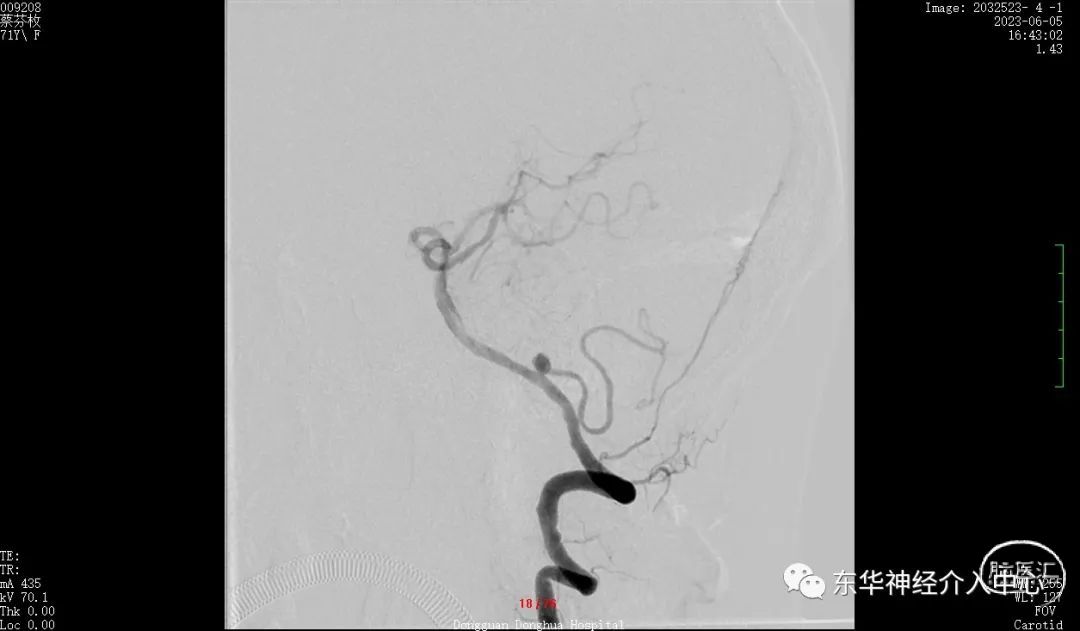

如此信心大增。继续填塞。终于满意的将动脉瘤栓塞,动脉瘤完全不显影。

换一个角度看弹簧圈的形态与动脉瘤的形态基本一致了。

继续换另外一个角度看瘤颈无任何残留。